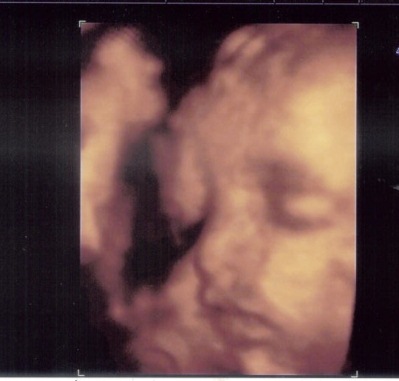

No ha visto la luz y ya conocemos su cara.

Hacia mediados de Agosto esperamos que la personita que lleva June vea la luz.

Pero ya tenemos imagen de su carita.